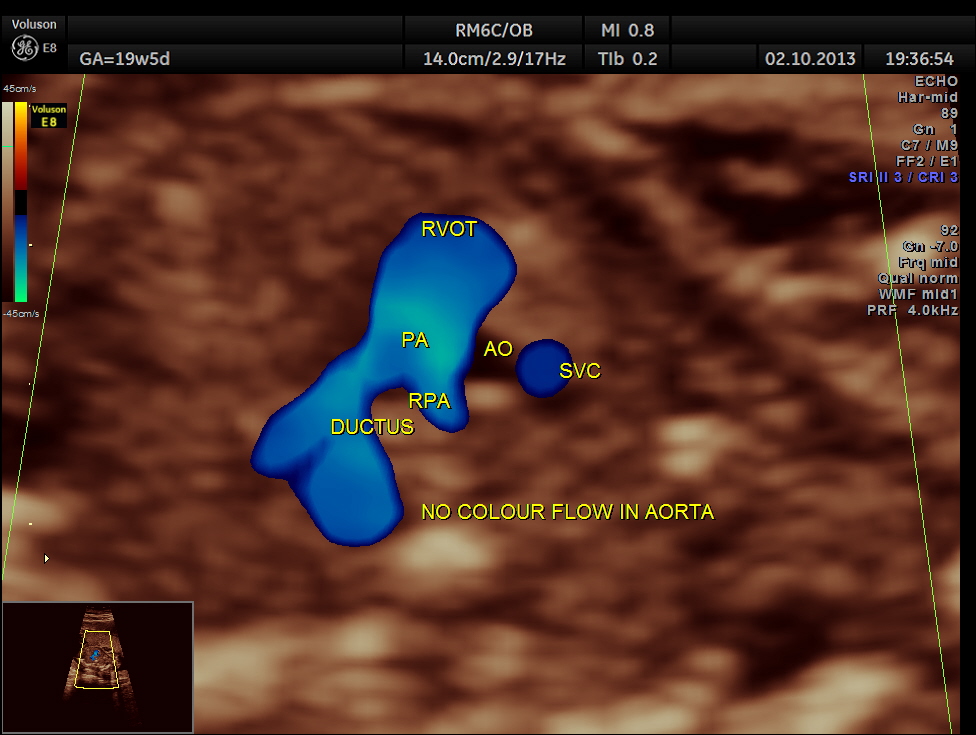

Aortic arch is progressively narrowed with the isthmus appearing very narrow. A flow reversal is also seen .